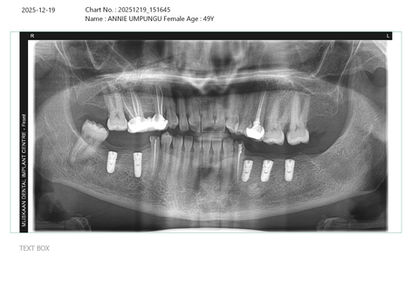

Une preuve de notre expertise : Voici un exemple concret d'une restauration complète réalisée récemment. Ce patient a reçu 11 implants dentaires au total, retrouvant une dentition parfaite et fonctionnelle à un prix incroyable, bien inférieur aux tarifs pratiqués en Europe ou en Amérique.